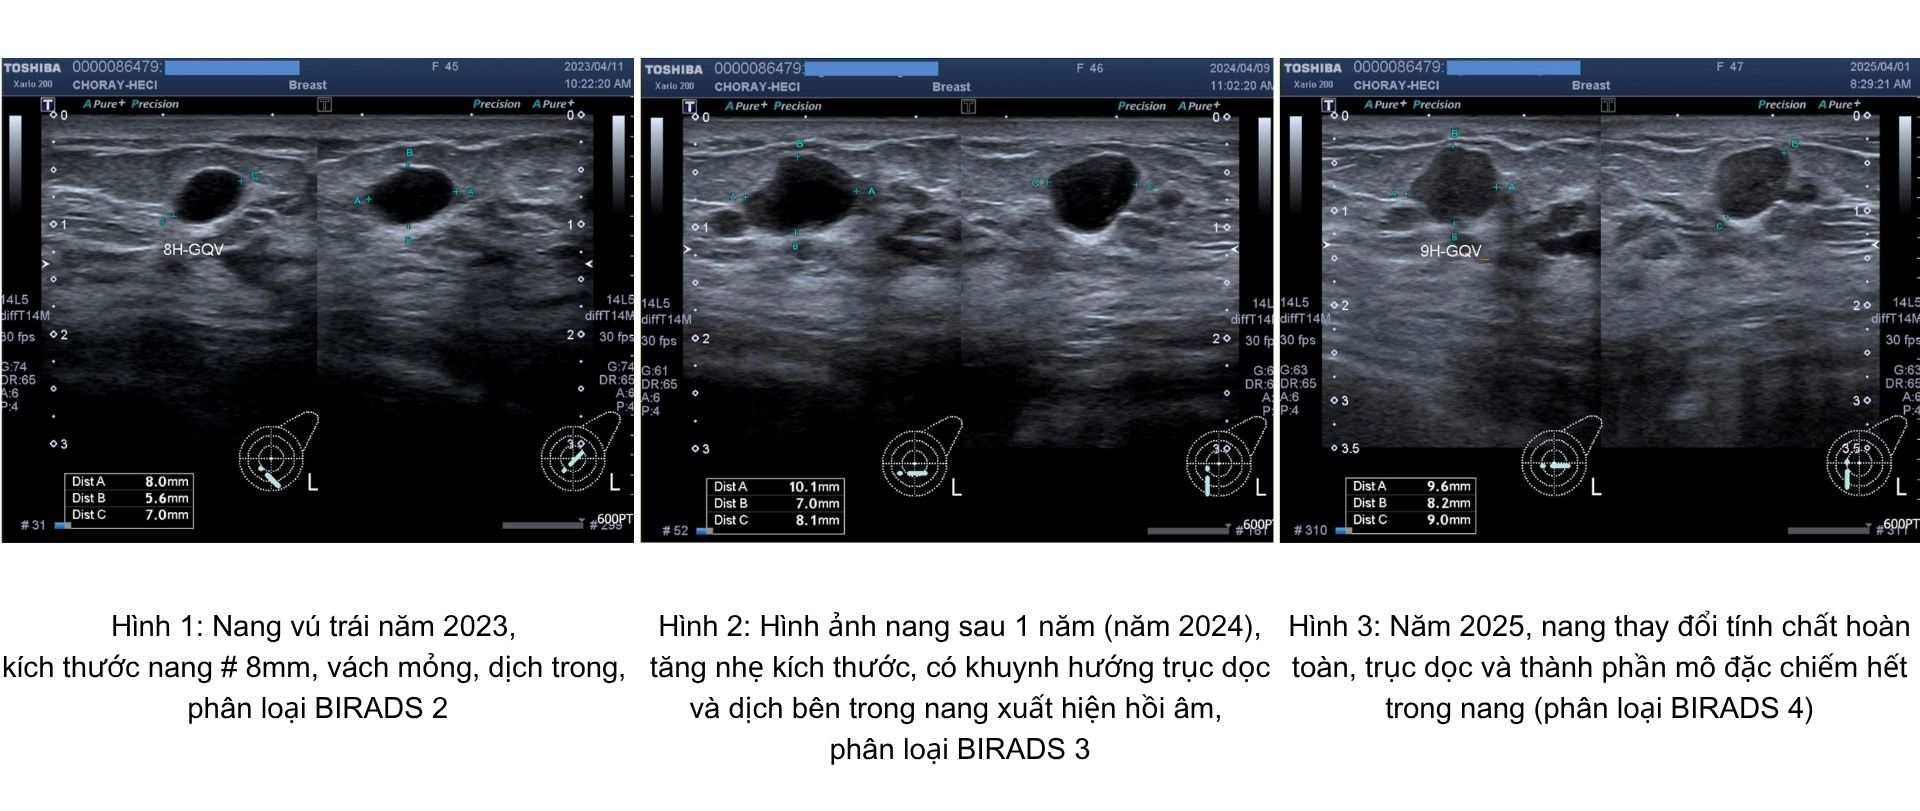

Chị N.T.H.V. (47 tuổi, ngụ TPHCM) đã kịp thời phát hiện khối u tuyến vú nghi ngờ chuyển ác tính nhờ thói quen tầm soát sức khỏe định kỳ tại Trung tâm Kiểm tra sức khỏe Chợ Rẫy Việt Nhật (HECI).

Năm 2023, khối u của chị được ghi nhận là nang lành (BIRADS 2), kích thước nhỏ, không có bất thường bên trong. Một năm sau, khối u tăng nhẹ kích thước, thay đổi hình thái và dịch bên trong có hồi âm (BIRADS 3). Tuy nhiên, do chưa đi tái khám đúng hẹn, đến năm thứ ba, khối u đã chuyển sang BIRADS 4, nghi ngờ ác tính cao, với thành phần đặc chiếm toàn bộ nang.